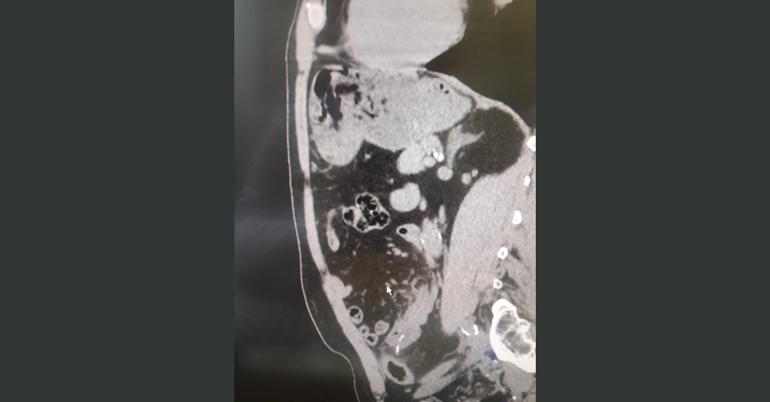

ქირურგიის ეროვნულ ცენტრში კომპიუტერული ტომოგრაფია წარმოებს ულტრათანამედროვე, მრავალშრიან კომპიუტერულ ტომოგრაფზე Toshiba aquilion RXL–ზე, რომელიც თავის კლასში უპირობო ლიდერია.

კლინიკის რადიოლოგმა ირაკლი გიგიაძემ შენიშნა, რომ წვრილი ნაწლავი უცხო სხეულით იყო დაზიანებული. დაუდგენელი სახეობის უცხო სხეული ნაწლავის სანათურიდან მუცლის ღრუში გამოდიოდა. პაციენტს ჩაუტარდა ლაპარასკოპია. მოიძებნა და ამოღებულ იქნა უცხო სხეული, ხოლო წვრილი ნაწლავის დაზიანებული უბანი გაიკერა.

უცხო სხეული, რომელიც ქირურგებმა პაციენტის წვრილი ნაწლავიდან ამოიღეს, აღმოჩნდა მეტალის მავთული (ჭურჭლის სახეხის შემადგენელი ნაწილი), რომლის ზომაც 4 სმ–ს შეადგენდა და კუჭ–ნაწლავში საკვებიდან მოხვდა.